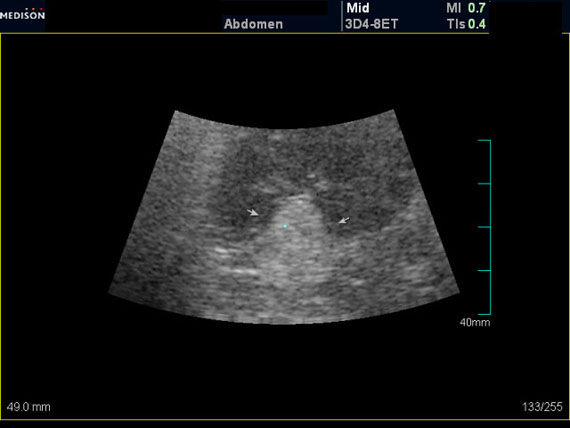

Случайная находка в нижней трети левой почки (не в полюсе, а по задне-медиальной поверхности).

Образование в левой почке

ПО УЗ-семиотике образование соответствует ангиомиолипоме (AML). По правилам в таких случаях необходимо выполнить КТ, доказать преимущественно жировой состав опухоли, затем проводить УЗ-наблюдение.

Согласен. Именно с таким диагнозом (ангиомиолипома) отправил на КТ. Особенностью случая ИМХО является заметный "выход" образования за контур почки (на 2/3 объема).

При ультрасонографии ангиомиолипома выглядит как округлое образование без капсулы с однородной внутренней эхоструктурой и четкими контурами; эхогенность ее чаще всего равна или чуть выше эхогенности перинефральной клетчатки [7]. Значительно реже эхогенность ангиомиолипом может быть равна эхогенности почечной паренхимы; такие опухоли состоят почти полностью из гладкомышечной ткани [8]. Иногда позади ангиомиолипомы может определяться слабая акустическая тень.